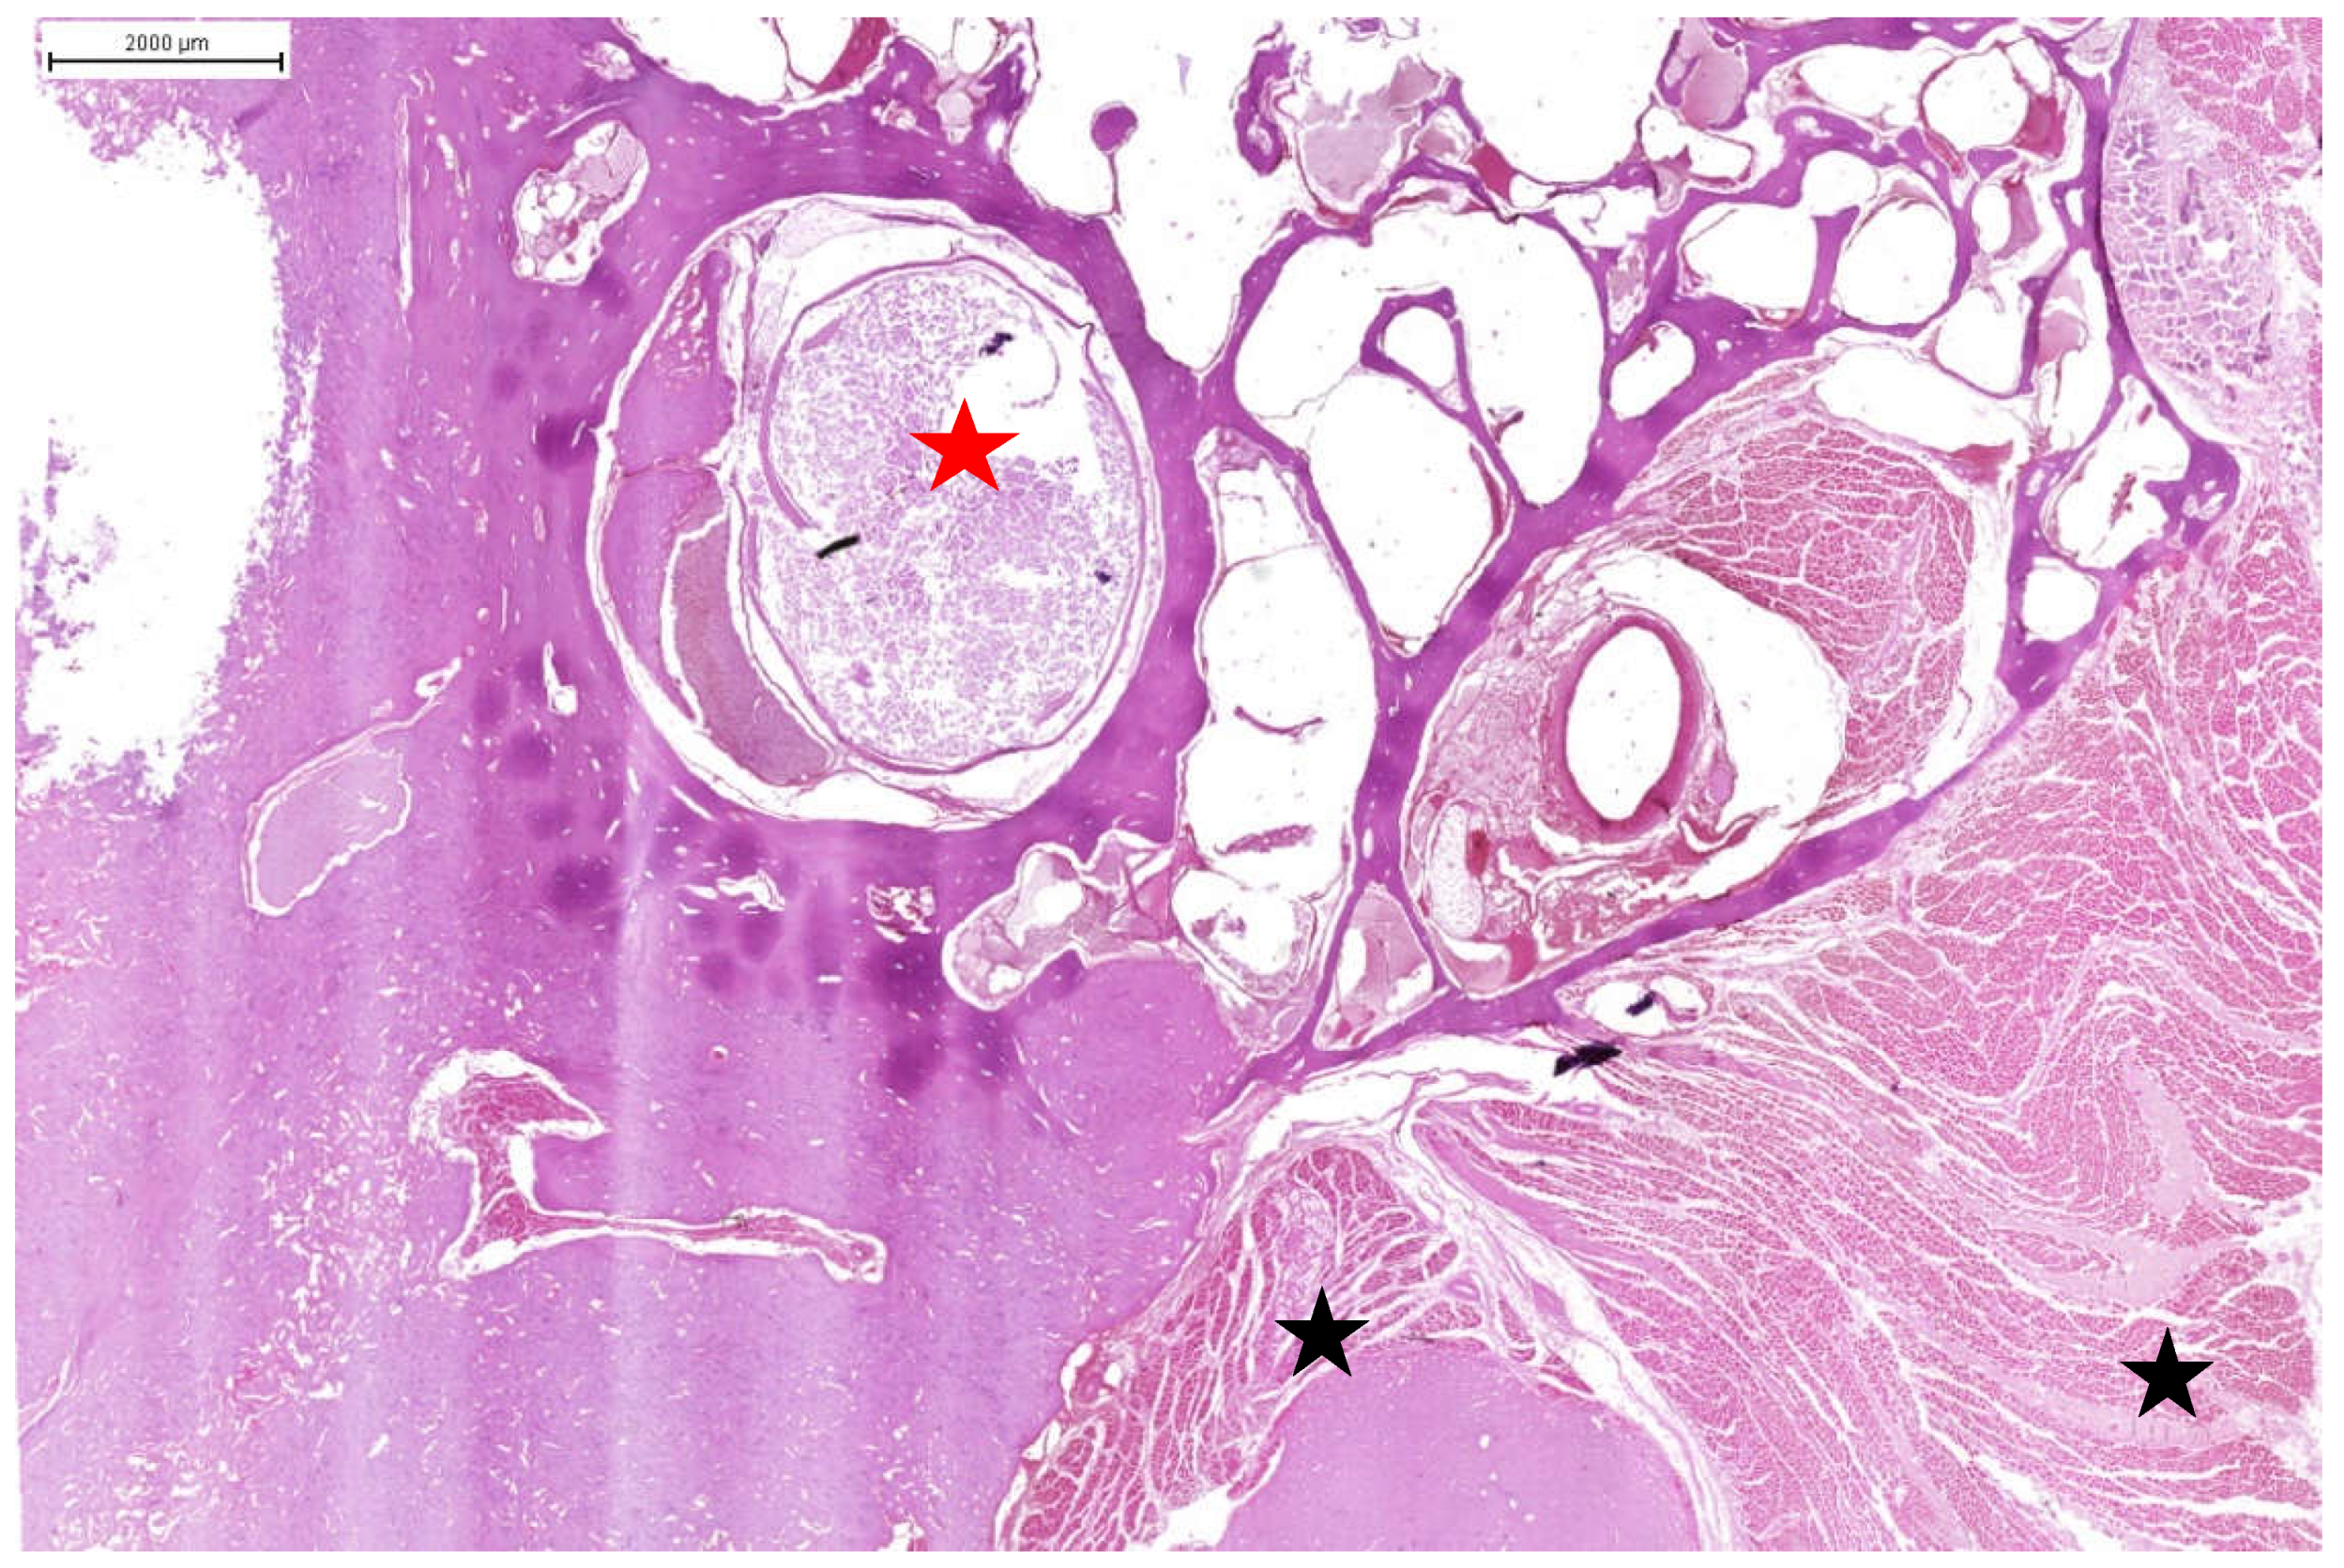

Histopathological examination confirmed the presence of a well-defined benign neoplasm derived from bone tissue arose from the body of the cervical vertebrae (Figure 6). The tumour was well circumscribed and consisted large area of irregular, disorganized bone trabeculae, usually surrounded by a layer of neoplastic osteoblasts (Figure 7 and Figure 8). Between the trabeculae well-vascularised connective tissue was observed, suggesting intense metabolic activity within the cancer. Histopathological examination of the tumour showed that the change was mild and derived from bone tissue. The tumour has been classified as an osteoma. The microscopic evaluation of the organs and tissues did not reveal any pathological changes or metastasis.

Figure 6. Domestic goose. Cervical vertebra with tumour. Visible central canal with spinal cord (red asterisk). Below, visible tumour mass originating from the body of the cervical vertebra (black asterisks). HE staining.